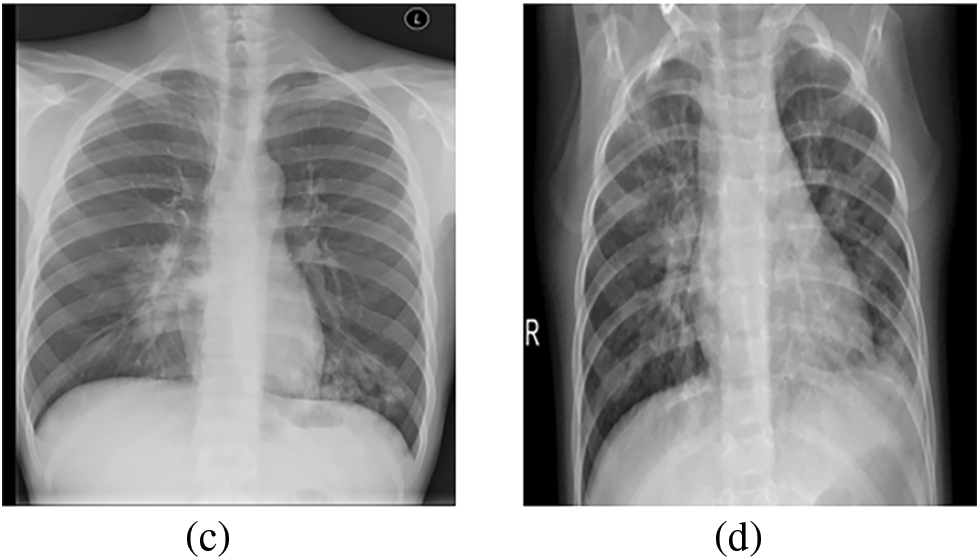

The dataset used in this work was collected by the researchers in [37]. In particular, it contains four classes. Namely these categories enclose positive COVID-19, negative COVID-19, viral pneumonia, and lung opacity cases. For the binary classification problem, 4000 images for the positive and negative COVID-19 classes were considered. To assess further the proposed models, a viral pneumonia class containing 1345 images, and a lung opacity class including 2000 images were added to address the multi-class classification problem. One should note that the resulting 7,345 grayscale images exhibit a resolution of 299 × 299 pixels. Fig. 1 shows samples from each class of the considered dataset.

Figure 1: (a) Sample of positive COVID-19 images. (b) Sample of negative COVID-19 images. (c) Sample of lung opacity images. (d) Sample of viral pneumonia images